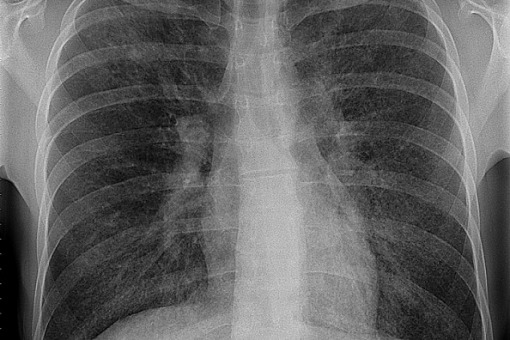

Rytuksymab dobrą opcją dla chorych z ciężką śródmiąższową chorobą płuc

Naukowcy zbadali skuteczność i bezpieczeństwo rytuksymabu w porównaniu z cyklofosfamidem podawanym dożylnie u pacjentów ze śródmiąższową chorobą płuc związaną z chorobą tkanki łącznej. Wyniki opublikowano w „The Lancet Respiratory Medicine”.

101 pacjentów w wieku od 18 do 80 lat z ciężką lub postępującą śródmiąższową chorobą płuc zostało losowo przydzielonych w stosunku do grupy otrzymującej rytuksymab (1000 mg w tygodniu 0. i 2., lek podawany dożylnie) lub cyklofosfamid (600 mg/m2 powierzchni ciała co 4 tygodnie dożylnie; w sumie 6 dawek). Pierwszorzędowym punktem końcowym była szybkość zmiany FVC po 24 tygodniach w porównaniu z wartością wyjściową.

Zarówno w grupie cyklofosfamidu, jak i rytuksymabu FVC uległo poprawie średnio o mniej więcej 40 ml, bez istotnej różnicy między grupami. W obu leczonych grupach zaobserwowano poprawę czynności płuc i jakości życia. Całkowite przeżycie, przeżycie wolne od progresji choroby i czas do niepowodzenia leczenia nie różniły się istotnie pomiędzy obiema grupami. Liczbowo mniej zdarzeń niepożądanych zgłosili uczestnicy otrzymujący rytuksymab (445 zdarzeń) niż ci otrzymujący cyklofosfamid (646 zdarzeń).

Lek jest tak samo skuteczny i o nieco większym profilu bezpieczeństwa – to wszystko udowodniono w dobrej jakości randomizowanym badaniu. Takie udokumentowanie z pewnością stanowi podstawę do włączenia rytuksymabu jako rutynowej opcji terapeutycznej u chorych ze śródmiąższową chorobą płuc.